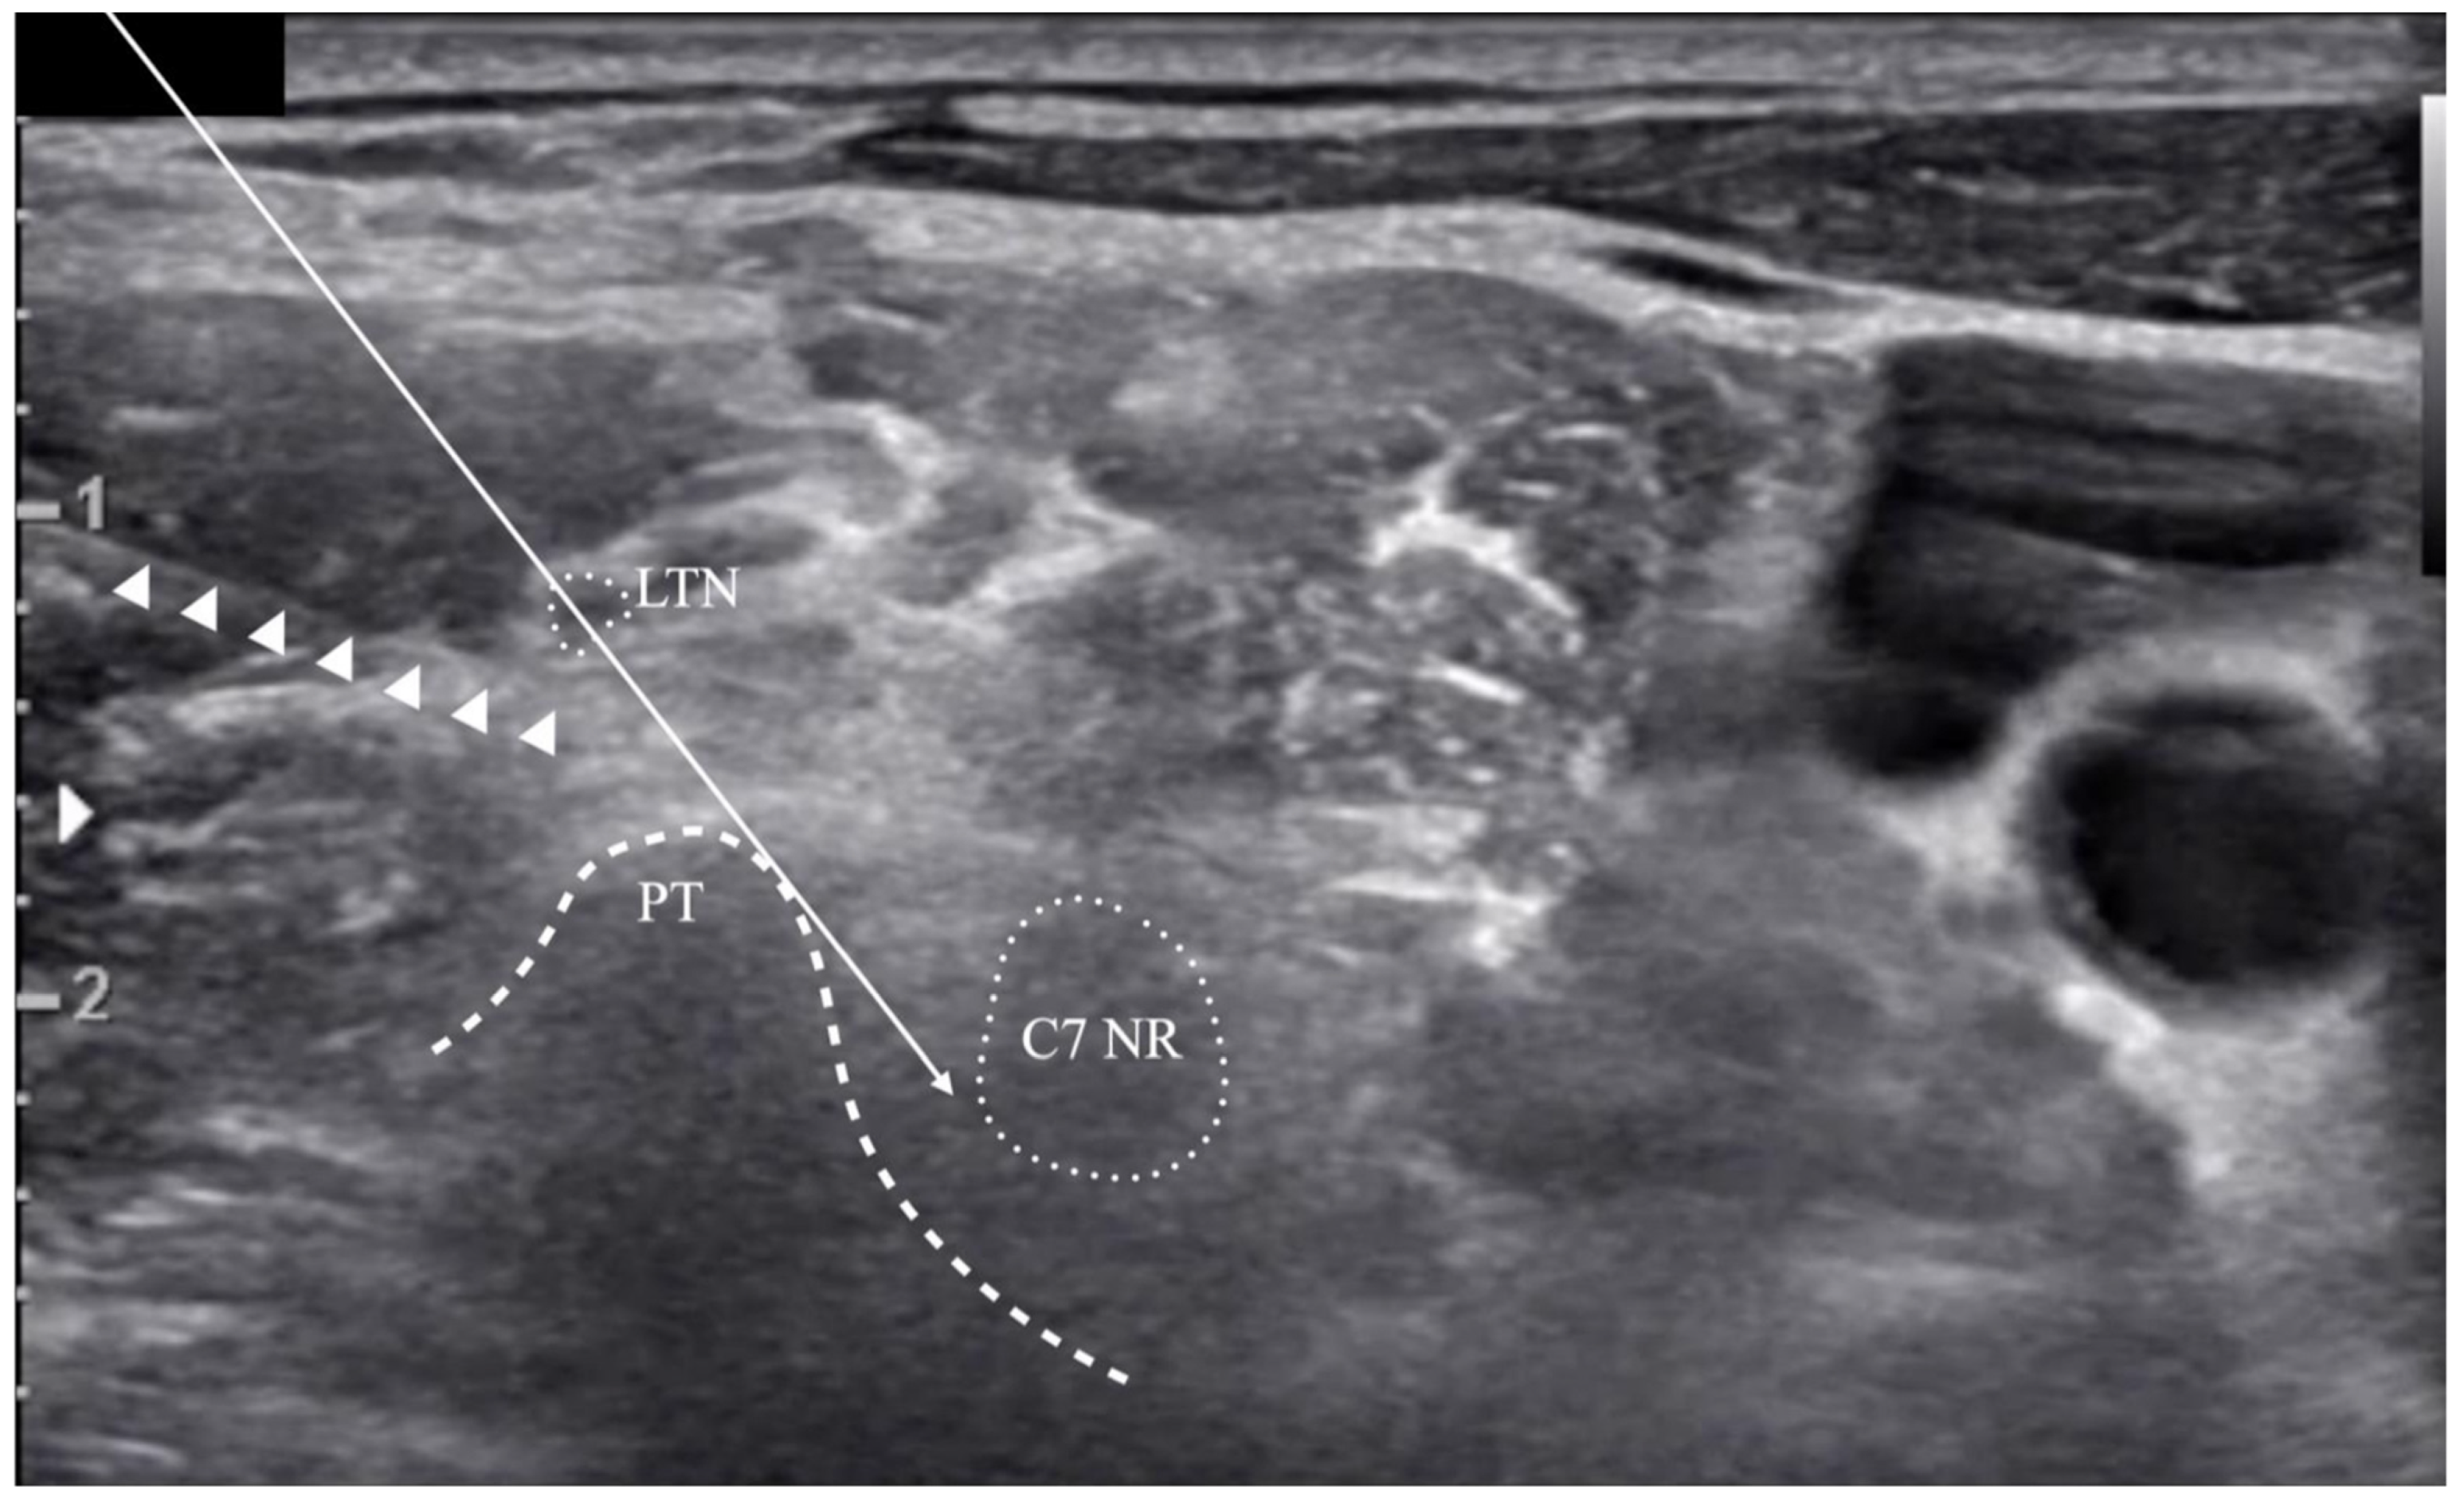

2.1. Ultrasound Image

indicates that it was outside the risk area in the simulated risk analysis. The LTN’s mean location and locational area estimated by the mean ± standard deviation (SD) are presented. The painted area indicates that the needle’s trajectory is expected to be associated with a high risk of LTN injury.